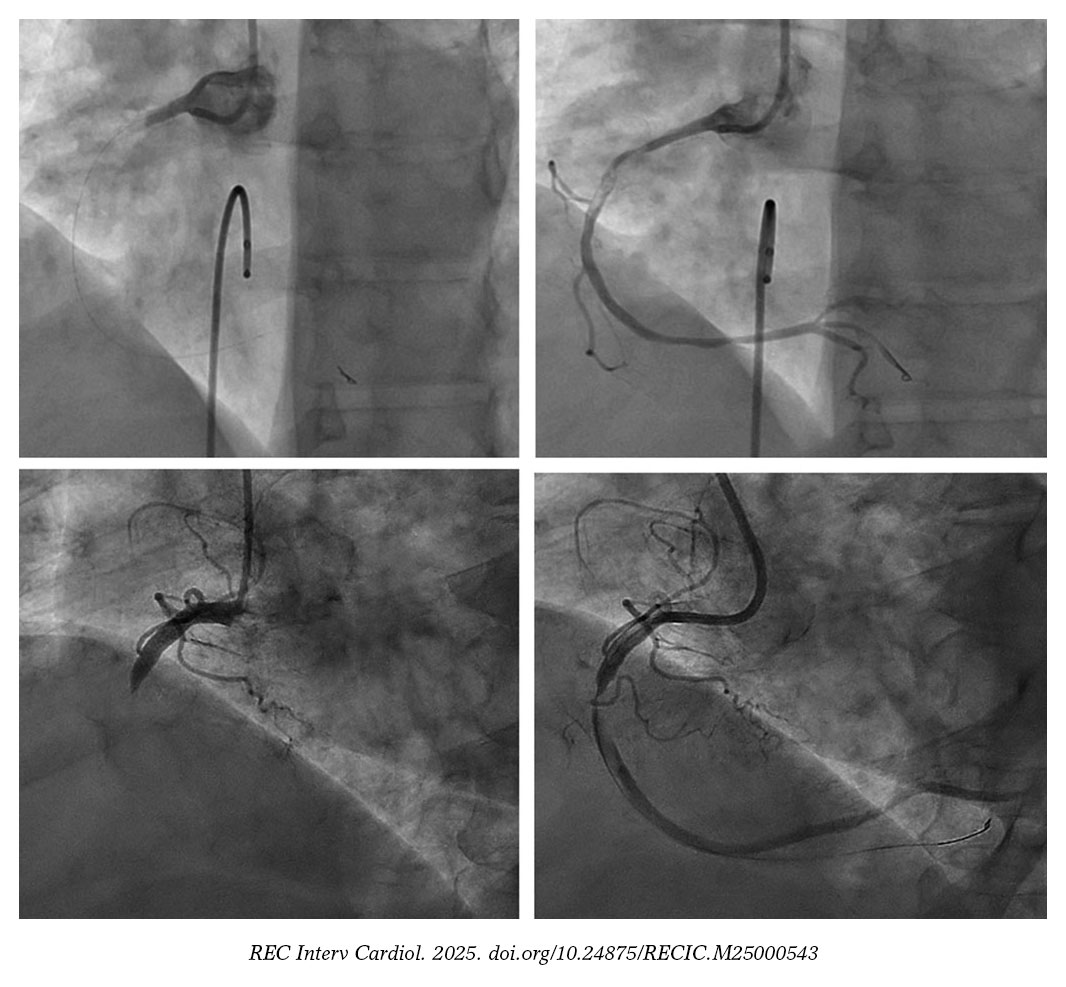

De toda la cohorte, 124 pacientes (95,4%) presentaron lesiones culpables con GCT. Previamente a la liberación de la energía láser, se informó de un grado de flujo TIMI 0 en 79 casos (60,8%) y TIMI 1 en 32 (24,6%). Tras la ELCA, se alcanzó un grado de flujo TIMI 2 y 3 en 45 (34,6%) y 66 (50,8%) casos, respectivamente; p < 0,001) (figura 1).

Figura 3. Hallazgos antes y tras la ELCA en 2 casos típicos de coronaria derecha con gran carga trombótica. ELCA: angioplastia coronaria con láser de excímeros.